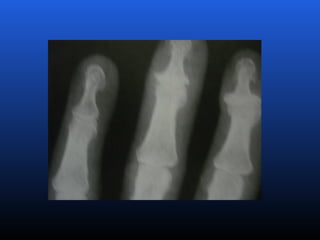

EROSIVA:Também conhecida como osteoartrose inflamatória.

Acomete as articulações IFD e IFP nas mãos, com FR (fator

reumatóide negativo)

PRIMÁRIA (idiopática): Ocorrena ausência de qualquer fator predisponente conhecido e se subdivide em duas categorias, localizada e generalizada (inclui 3 ou mais áreas). SECUNDÁRIA: É aquela em que se reconhece uma causa ou um fator preexistente. EROSIVA:Também conhecida como osteoartrose inflamatória. Acomete as articulações IFD e IFP nas mãos, com FR (fator reumatóide negativo) ClassificaçãoClassificação